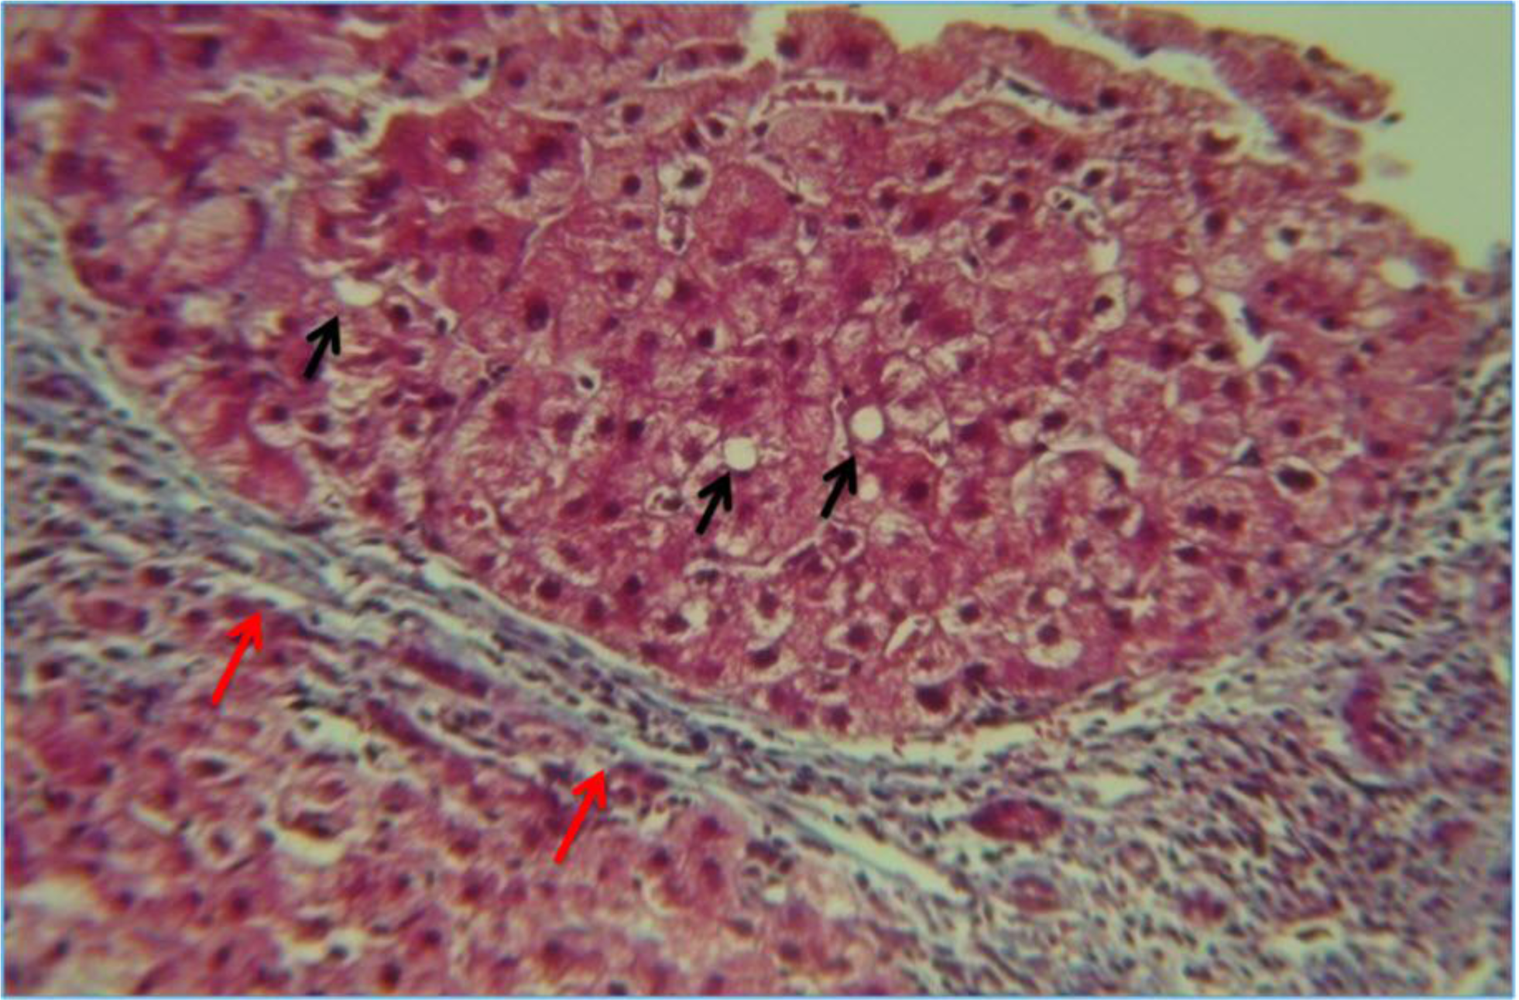

5.1. Steatosis and Steatohepatitis

5.2. Alcoholic Hepatitis

5.3. Fibrosis and Cirrhosis